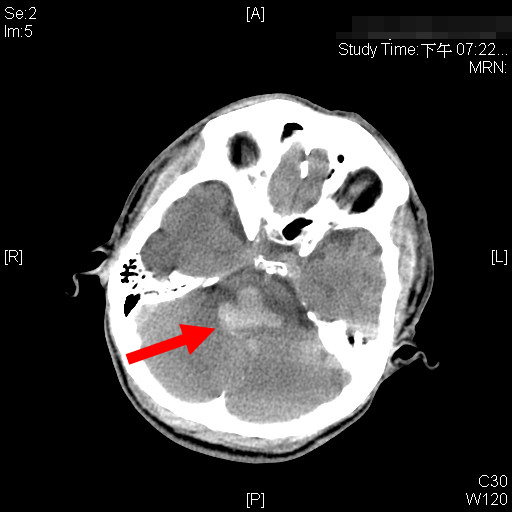

原发性脑干出血

是一种特殊类型的脑出血,多数与高血压病有关,约占脑出血的10%,其发病急剧,危害极大,尤其是发病后昏迷发生早、程度深,持续时间长,并发症多,其死亡率高达80%以上,重残和植物生存占相当比例。保持呼吸道通畅,维持内环境的平衡、积极防治并发症的发生以及重点、精心、全面的护理是提高原发性脑干出血生存率的关键。

脑干出血临床表现特点

1、意识障碍出现早、深和持续时间长;

2、瞳孔变化多样,如针尖样瞳孔、眼球震颤、眼球活动受限等。

3、病情变化多而快:可由偏瘫发展为四肢瘫,病理征由一侧发展为双侧。

4、重症者并发症多:如呼吸衰竭、体温不升和高热、肺部感染、上消化道出血、血糖升高、发热等。

5、预后差;除少数脑干出血量大,破入脑室,引起急性梗阻性脑积水者,需行脑室外分流术外,多数主要采用保守治疗。因此,质量的好坏直接与患者预后相关。

6、该部位发生出血,即使微小的出血和血肿可引起严重的后果。其临床表现危重,易出现昏迷、中枢性呼吸循环衰竭、脑内脏综合征、脑疝、MODS等致命性并发症。

7、随着临床上高分辨的CT和MRI的普及,脑干出血能及时诊断。尤其是针对脑出血,开展了全面的个体化、规范化的综合治疗,使部分病情得以控制,有效降低病死率与致残率。